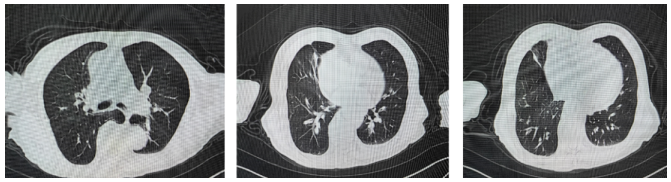

12月22日胸部CT:双肺多发肺大疱,双肺散在实变,右肺中叶内侧段节段性肺不张并支气管扩张,双肺支气管管壁增厚,管腔狭窄,左右主支气管、双肺支气管内痰栓形成,双侧胸膜增厚。

12月26日胸部CT:与12月22日相比,双肺实变较前增多,新增双侧胸腔少量积液图1。颅脑CT:右侧半卵圆中心腔隙灶,脑白质疏松,脑萎缩。血气分析pH 7.42,PaO2 93 mmHg,PaCO2 42 mmHg,HCO3- 26.8 mmol/L,P/F 265.7 mmHg(经鼻高流量氧疗)。

图1  胸部CT上图:2022-12-22,下图:2022-12-26